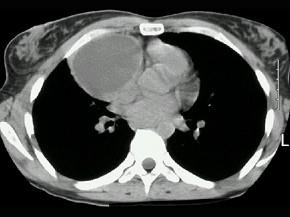

问题 女,18岁,自感胸闷,X线检查见纵隔占位,CT检查如图,最可能的诊断为 ( )

选项 A、淋巴瘤 B、下纵隔胸腺瘤 C、上纵隔胸腺瘤 D、胸内甲状腺瘤 E、纵隔畸胎瘤

答案 E